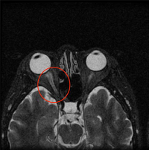

視力障害や視野障害などの視覚系障害、複視を含む眼球運動障害、眼瞼下垂や眼瞼痙攣などの眼瞼疾患や瞳孔の障害などにおいて眼科的検査をすすめながら診断および治療をおこなっていく分野が神経眼科です。

原因不明の視力障害などの原因が全身疾患に関係がある場合が多々あります。また複視の原因が重症筋無力症、甲状腺眼症、脳腫瘍や神経麻痺など、眼球以外に原因がある場合も、眼にしか障害がでない場合も多く神経眼科医の役割は大きいと思われます。

1.視交叉近傍圧迫性視神経症における構造と機能の関係

2.視神経・視路疾患の診断および治療効果に関する研究